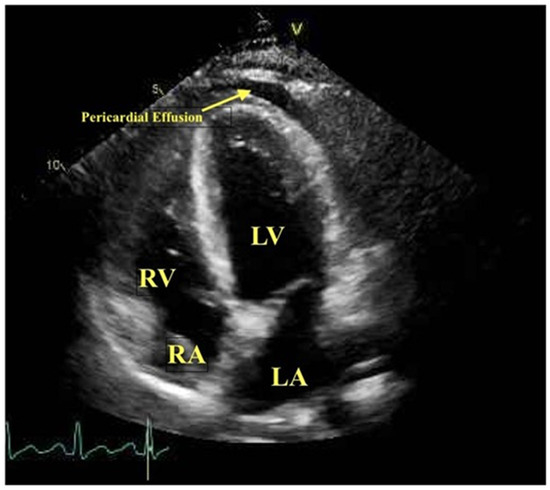

- Trogen, B.; Gonzalez, F.J.; Shust, G.F. COVID-19-Associated Myocarditis in an Adolescent. Pediatric Infect. Dis. J. 2020, 39, e204–e205. [Google Scholar] [CrossRef]

- Goerlich, E.; Minhas, A.S.; Mukherjee, M.; Sheikh, F.H.; Gilotra, N.A.; Sharma, G.; Michos, E.D.; Hays, A.G. Multimodality Imaging for Cardiac Evaluation in Patients with COVID-19. Curr. Cardiol. Rep. 2021, 23, 44. [Google Scholar] [CrossRef]